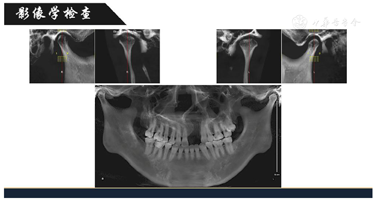

影像学检查:治疗前曲面体层片可见:18,28,38,48牙胚,牙槽突及硬腭裂隙至鼻腔。CBCT可见关节髁突在关节窝中位置基本正常,髁突关节面不圆滑有明显凹陷,但骨皮质尚连续,见图3。